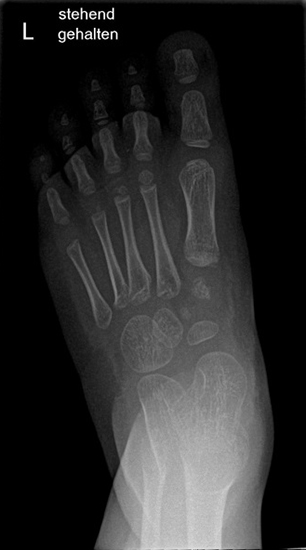

Röntgen Fuß AP und seitlich im Stand oder belastungssimuliert (Abb.1,2).

• Röntgen des dargestellten Falles 3 Monate post OP (Bild 25,26)